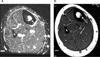

Methods: A total of 211 male and female collegiate track and field and cross-country athletes were followed prospectively through their competitive seasons. All athletes had preparticipation history, physical examination, and anthropometric measurements obtained annually. An additional questionnaire was completed regarding nutritional behaviors, menstrual patterns, and prior injuries, as well as a 3-day diet record. Dual-energy X-ray absorptiometry was performed at baseline and each year of participation in the study. Athletes with clinical evidence of bone stress injuries had plain radiographs. If radiograph findings were negative, MRI was performed. Bone stress injuries were evaluated by 2 independent radiologists utilizing an MRI grading system. The MRI grading and risk factors were evaluated to identify predictors of time to return to sport.

Results: Thirty-four of the athletes (12 men, 22 women) sustained 61 bone stress injuries during the 5-year study period. The mean prospective assessment for participants was 2.7 years. In the multiple regression model, MRI grade and total-body bone mineral density (BMD) emerged as significant and independent predictors of time to return to sport. Specifically, the higher the MRI grade (P = .004) and lower the BMD (P = .030), the longer the recovery time. Location of the bone injury at predominantly trabecular sites of the femoral neck, pubic bone, and sacrum was also associated with a prolonged time to return to sport. Female athletes with oligomenorrhea and amenorrhea had bone stress injuries of higher MRI grades compared with eumenorrheic athletes (P = .009).